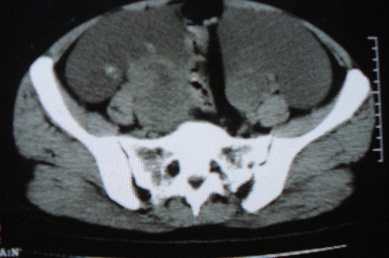

标题: CT8388:女,48岁。感腹胀一周,请会诊

ct10755,女,48岁。感腹胀一周入院。

考虑右侧卵巢囊腺癌并腹腔转移、子宫肌瘤

支持右侧卵巢囊腺癌并腹腔转移

考虑右侧卵巢囊腺癌并腹腔转移可能性大、子宫肌瘤

支持:右侧卵巢囊腺癌并腹腔转移,或囊腺瘤破裂腹腔种植。

支持:右侧卵巢囊腺癌并腹腔转移、腹水、盆腔积液。